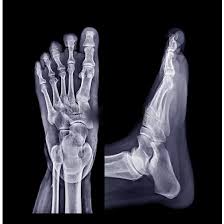

X-Ray Right Leg AP and Lateral

At Medifyhome, we offer detailed X-ray imaging of the right leg using both anteroposterior (AP) and lateral views. This dual-angle approach provides a complete picture of the leg’s bones and joints, crucial for diagnosing fractures, joint issues, infections, and other abnormalities. Our partnership with NABL and NABH-certified labs guarantees top-tier accuracy and reliability. With affordable rates and expert service, you can confidently manage your health with our comprehensive diagnostic support.

An X-Ray Right Leg AP and Lateral is a diagnostic imaging procedure that captures two views—front-to-back (anteroposterior) and side (lateral)—of the right leg.

This helps provide a comprehensive assessment of the bones, joints, and surrounding tissues for injuries or abnormalities.Why is it Done?